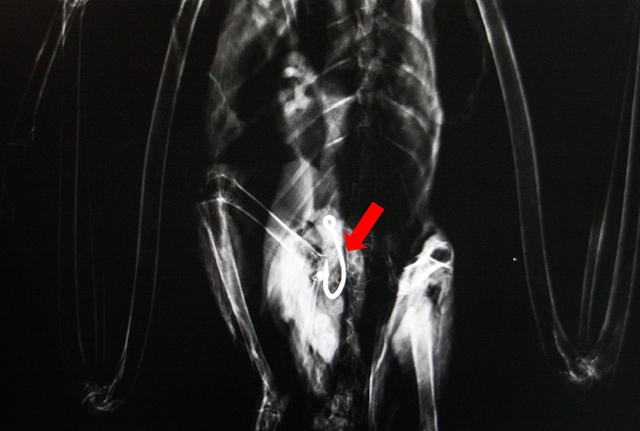

Esta ave ingressou com um fio preso no bico. Sem conseguir visualizar a origem, foi realizado um Raio-X que nos mostrou a existência, e por sua vez, localização, de um anzol no estômago do animal.